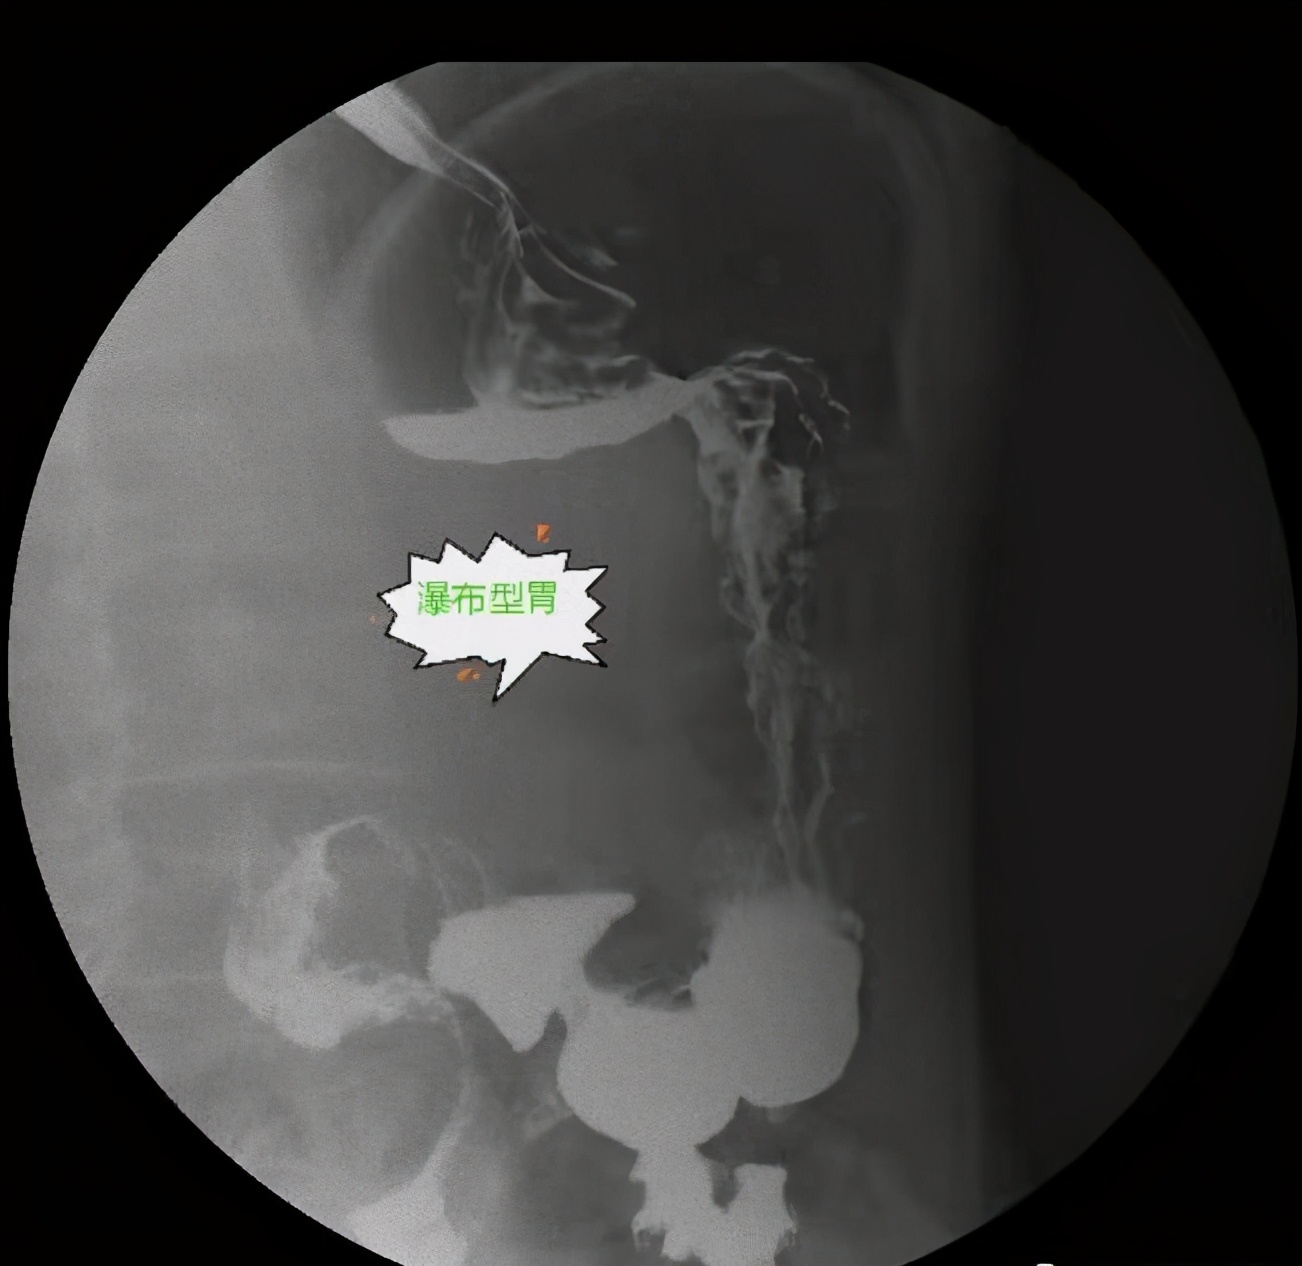

检查中,放射科医生发现,患者的胃底与胃体间的胃后壁上形成一个弯曲,钡剂在此两部分内形成液平面;确定是“瀑布型胃”的病人。“正常情况下人在吃喝食物后,食物经食道进入胃内,胃就像一个口袋一样,袋口朝上,食物直接因为重力而落入袋底,然后从胃内排空。”该院放射科代欢欢医生介绍,胃的形状与体型、张力和神经功能状态相关。常见的有四种类型:牛角型冒着中类型的胃多见于肥胖型人,胃的张力高,呈横位,角切迹不明显。第二种是钩型胃,它多见于适中体型的人,也是最常见的类型。第三种为长型胃又称无力型胃,多见于瘦长型人,胃的位置和张力都较低。而第四种瀑布型胃,这种胃型较为少见,胃底呈囊袋状向后倾,检查时钡剂先进入后倾的胃底,满后溢入胃体,犹如瀑布。

“患者吃完饭后出现胃胀的症状,主要是由瀑布型胃所致”武汉市第四医院消化内科主治医师郭秋霞介绍,“瀑布胃”患者的胃好像一个没有撑好的口袋,食物进入胃内后,先落入胃上部形成的较大的褶皱中,食物只有将这个褶皱填满后,才会逐步溢出,像“瀑布”一样流下,落入胃袋内,此后胃才能工作进行排空。沉积在小袋内的食物不易被排空到,如辛辣、油腻食物较长时间滞留,可对局部的胃黏膜产生较强的刺激,食物滞留后也易发酵使患者产生胃胀感,有时还会促使胃酸返流入食管产生反酸或烧灼感。